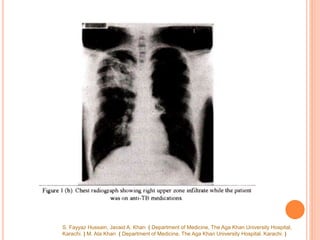

 Six months later, while still on anti-TB drugs, he

developed recurrence of symptoms with right

pleuritic chest pain, fever, cough, wheeze and

hemoptysis. Repeat chest x-ray showed infiltrates

in right lung (Figure ib).